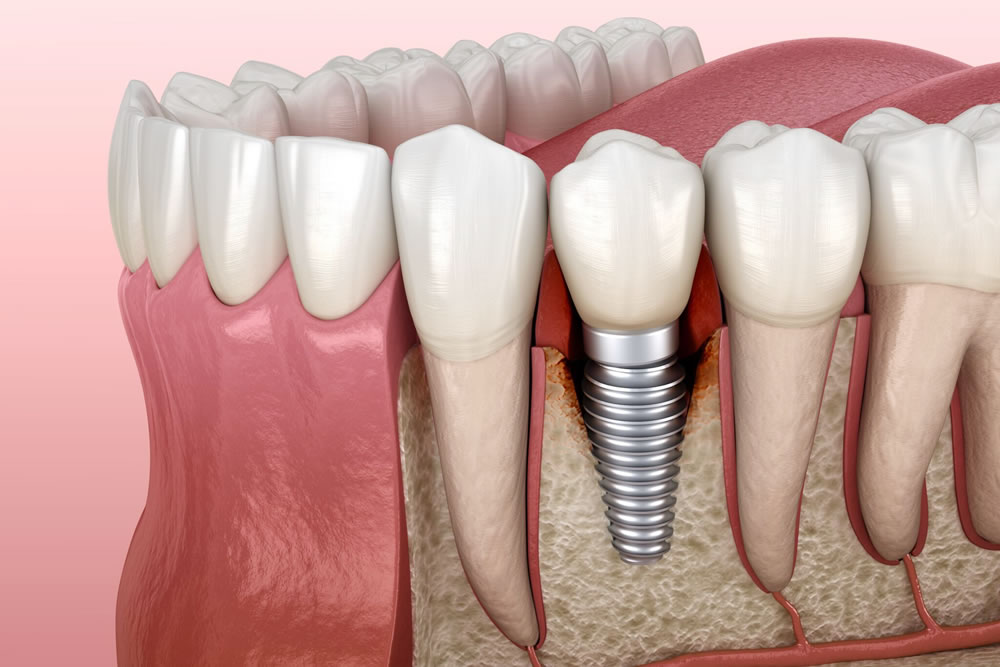

インプラント治療の基本構造

まず、インプラントは主に以下の3つの部品から成り立っています。

インプラント体(人工歯根):チタン製で骨に埋め込まれる

アバットメント:人工歯とインプラント体をつなぐ中間パーツ

上部構造(クラウン):見た目の歯となる人工歯

これらを段階的に設置するため、治療もいくつかの工程に分かれています。